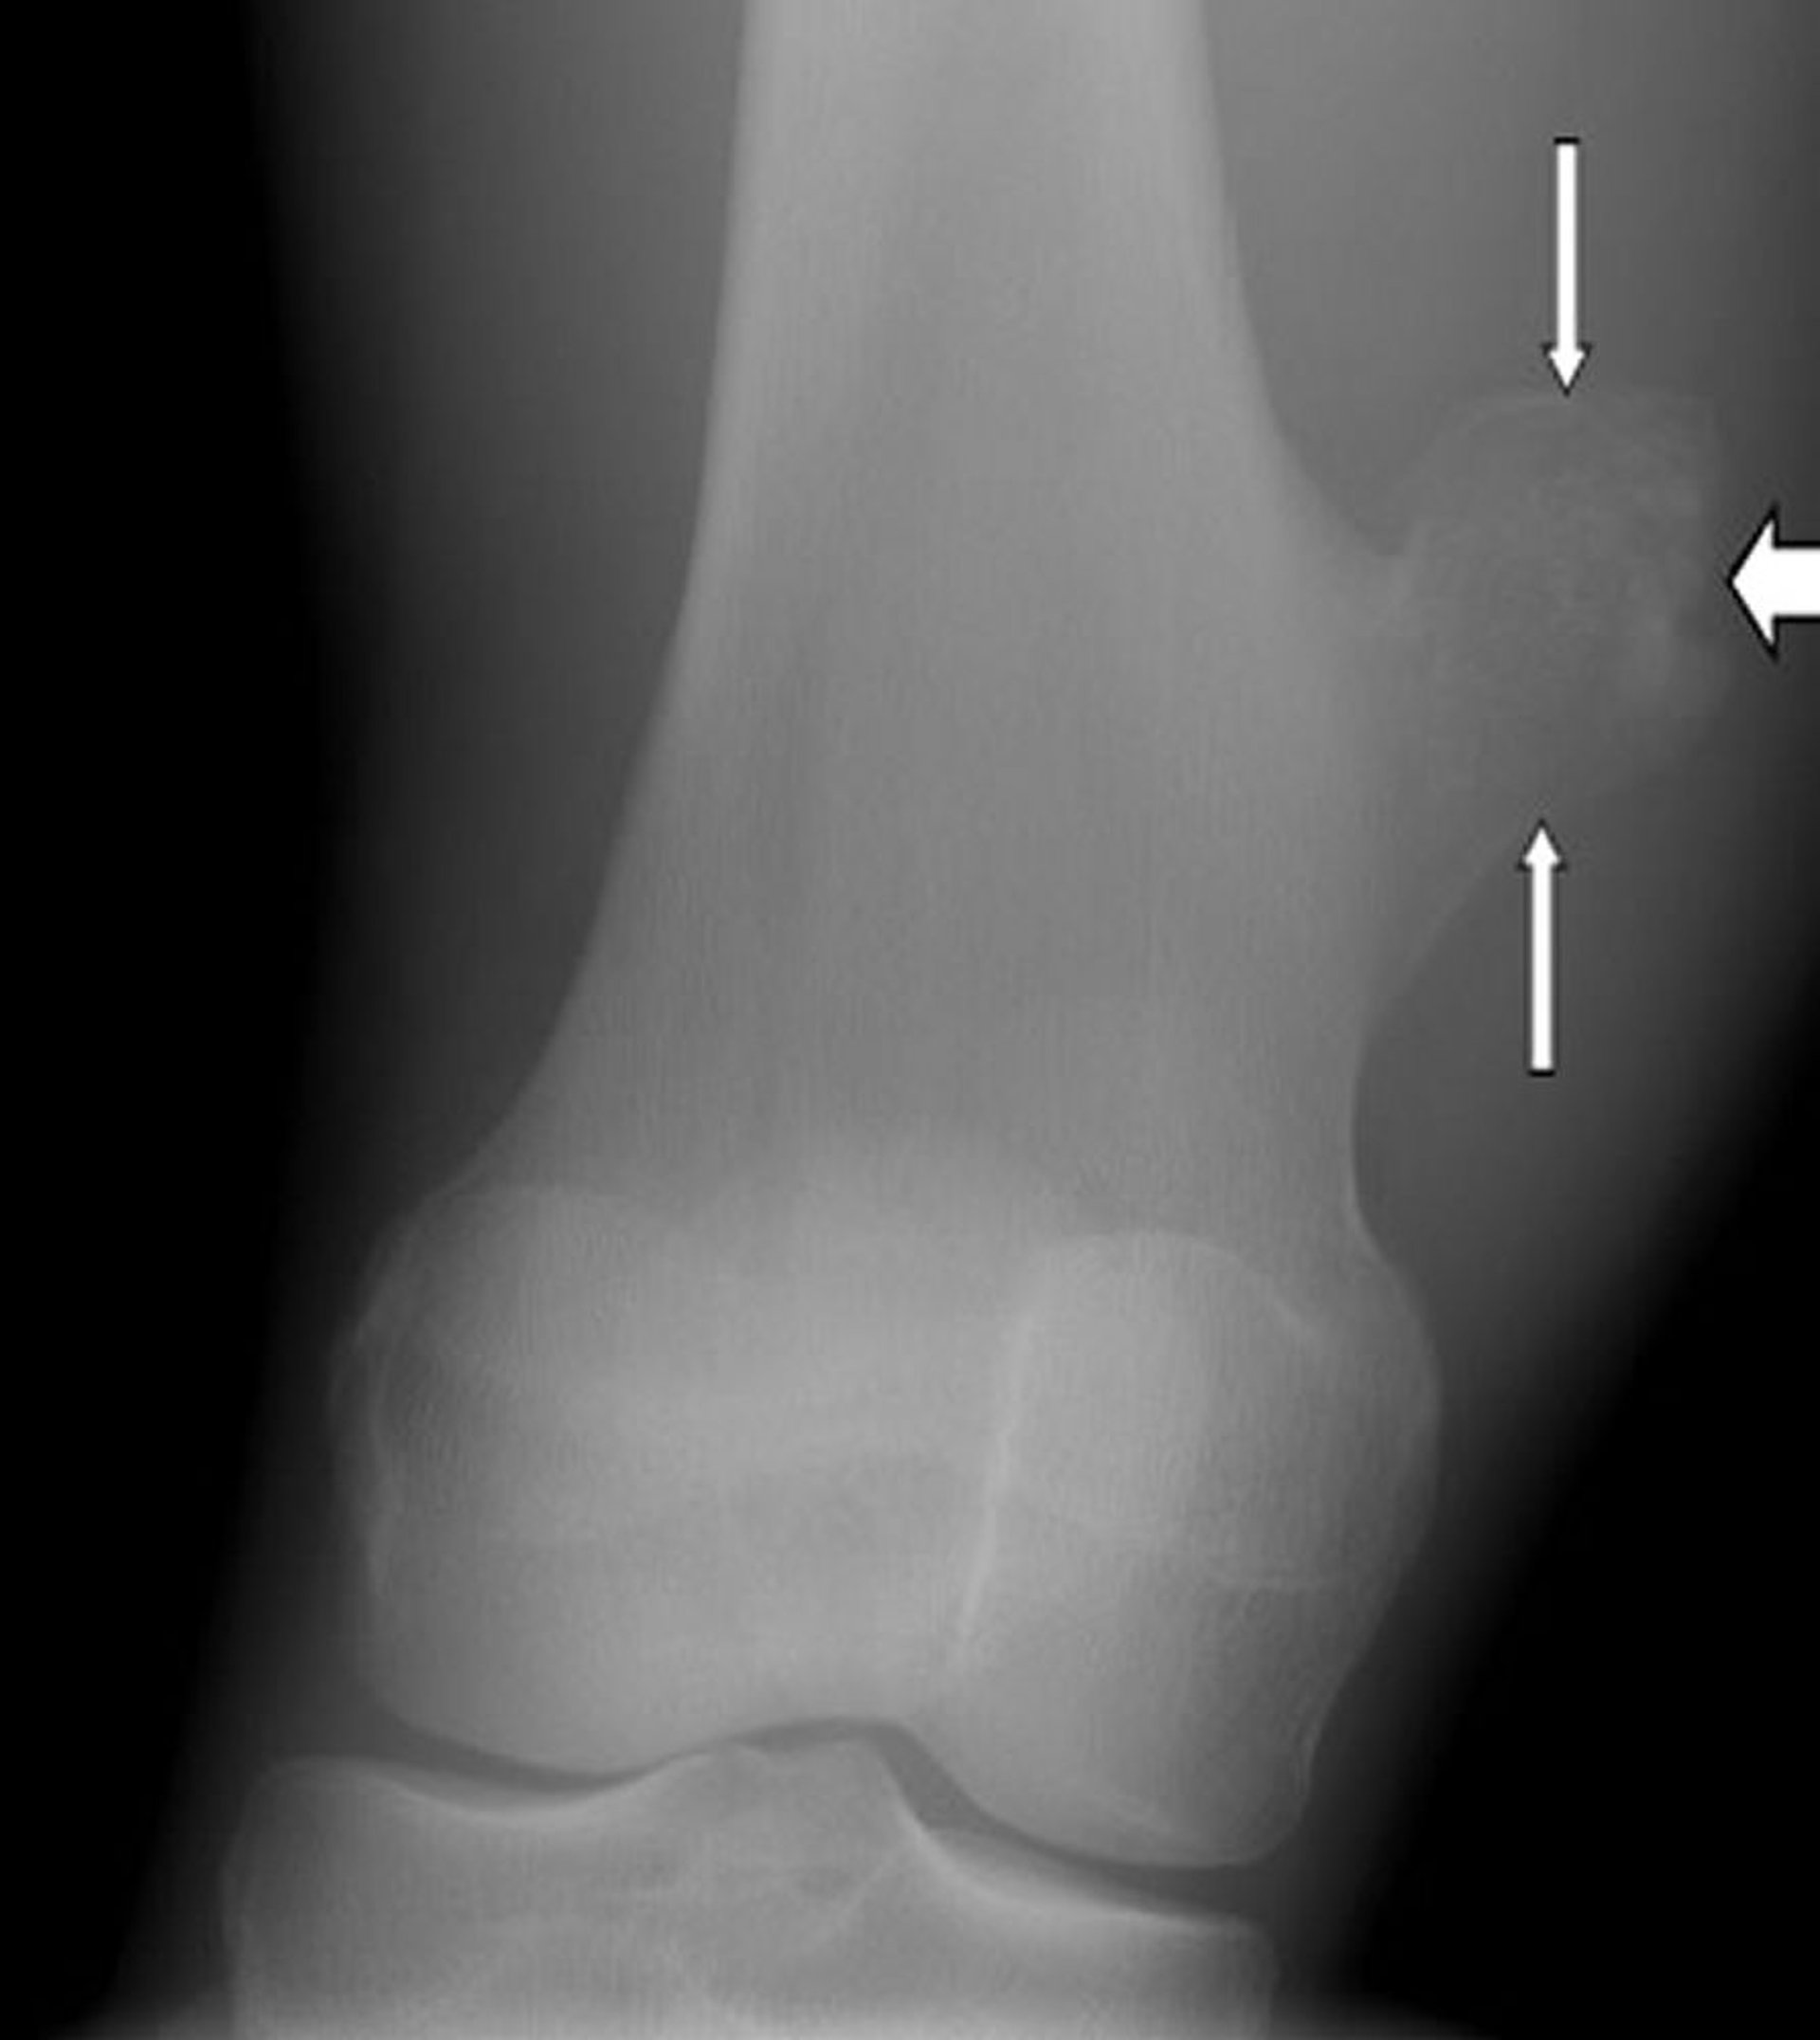

ورم عظمي غضروفي في الركبة

تُظهر هذه الصورة للركبة ورمًا عظميًا غضروفيًا، وهو نمو على سطح عظم الفخذ (اتجاه السهم) فوق مفصل الركبة.

جرى استخدام الصورة بعد موافقة أصحابها Michael J.Joyce, MD, and Hakan Ilaslan, MD.